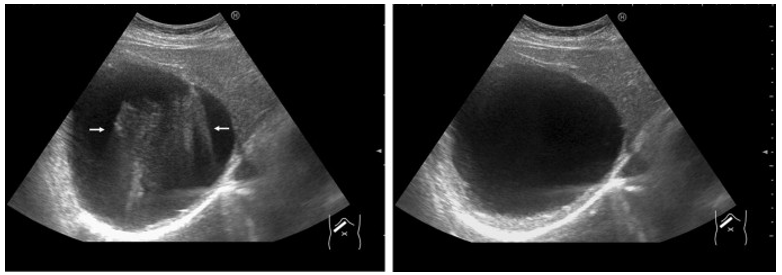

Simple Reverberation Artifact

Sound bounces between the transducer and a strong specular reflector, or between two strong specular reflectors.

Often called “reverb.”

More common in superficial tissues where the sound beam has not been attenuated.

Commonly noted in anechoic structures.